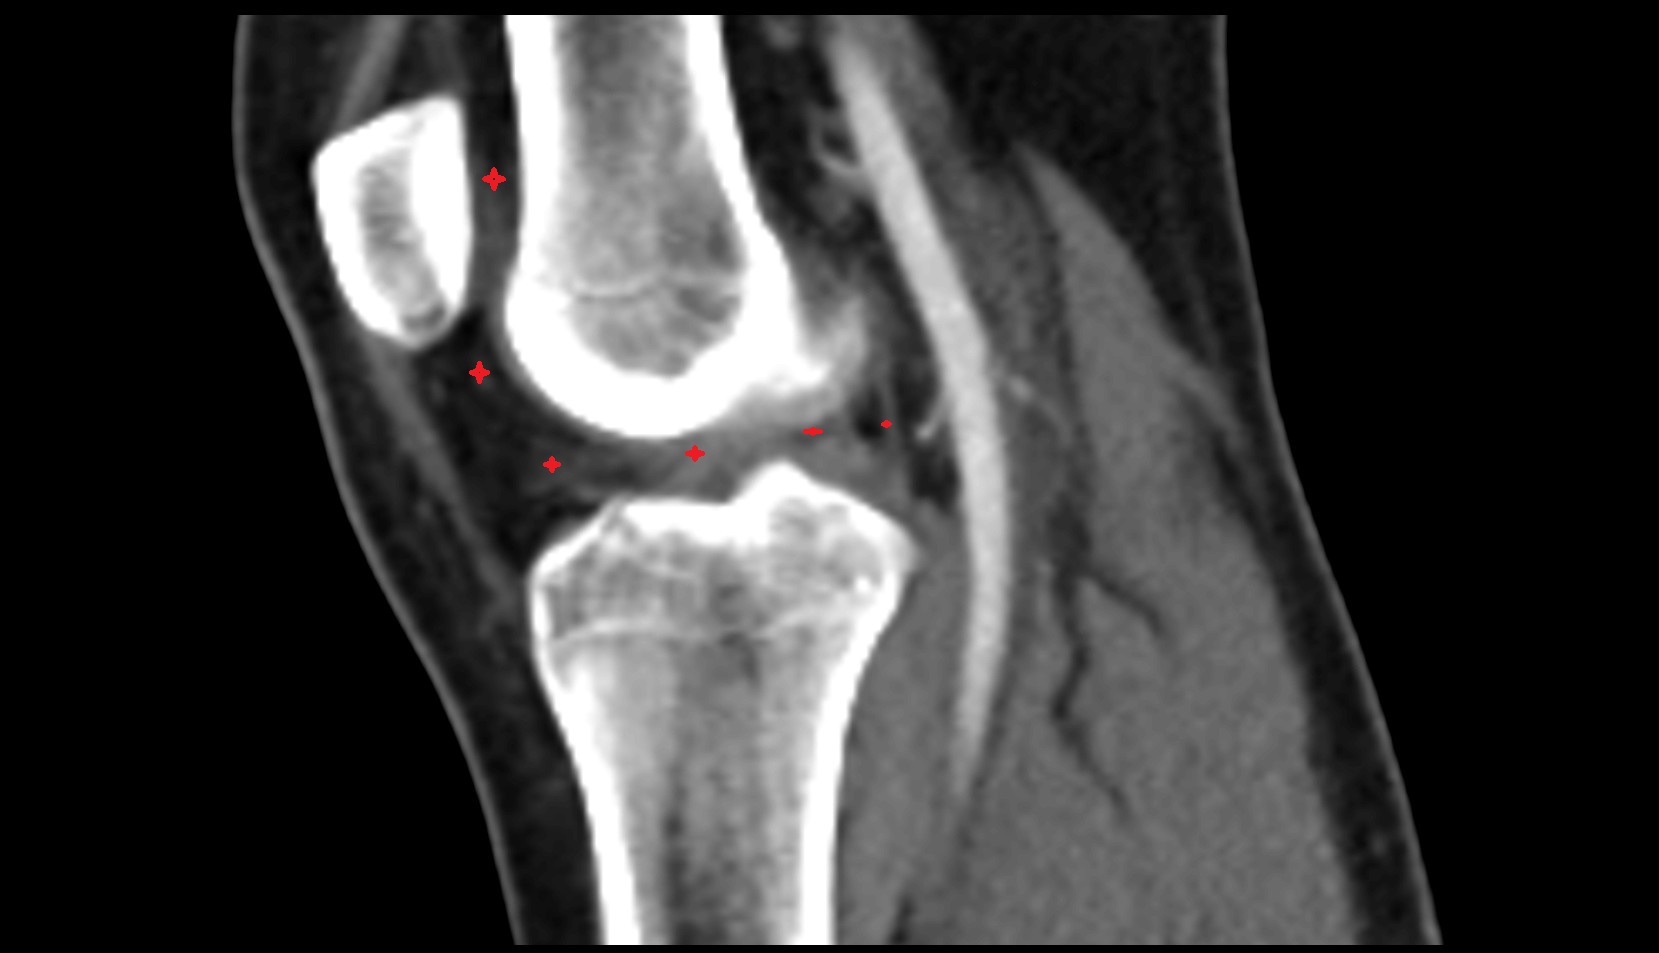

- Medial epicondyle of femur

- Lateral epicondyle of femur

- Lateral condyle of femur

- Medial condyle of femur

- Medial tibial plateau

- Lateral tibial plateau

- Knee Joint